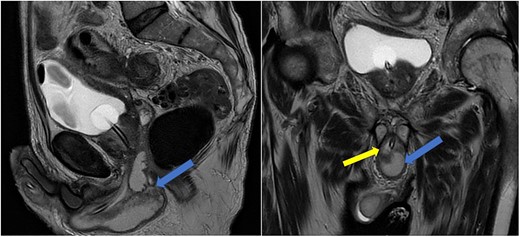

Case 2: T2-weighted sagittal MRI image demonstrating a complex, cystic perineal collection (blue arrow), seen in relation to one of the corpus cavernosa (yellow arrow).

He was put on an empirical course of ciprofloxacin to treat a presumed complicated UTI, and a pelvic MRI was requested. Urine culture grew an Enterobacter cloacae organism. The MRI scan revealed a 7 × 3 cm perineal collection inferior to the prostate and adjacent to the membranous urethra, with increased wall enhancement and fluid with restricted diffusion, with a diagnosis of Cowper’s syringocele (Fig. 3).